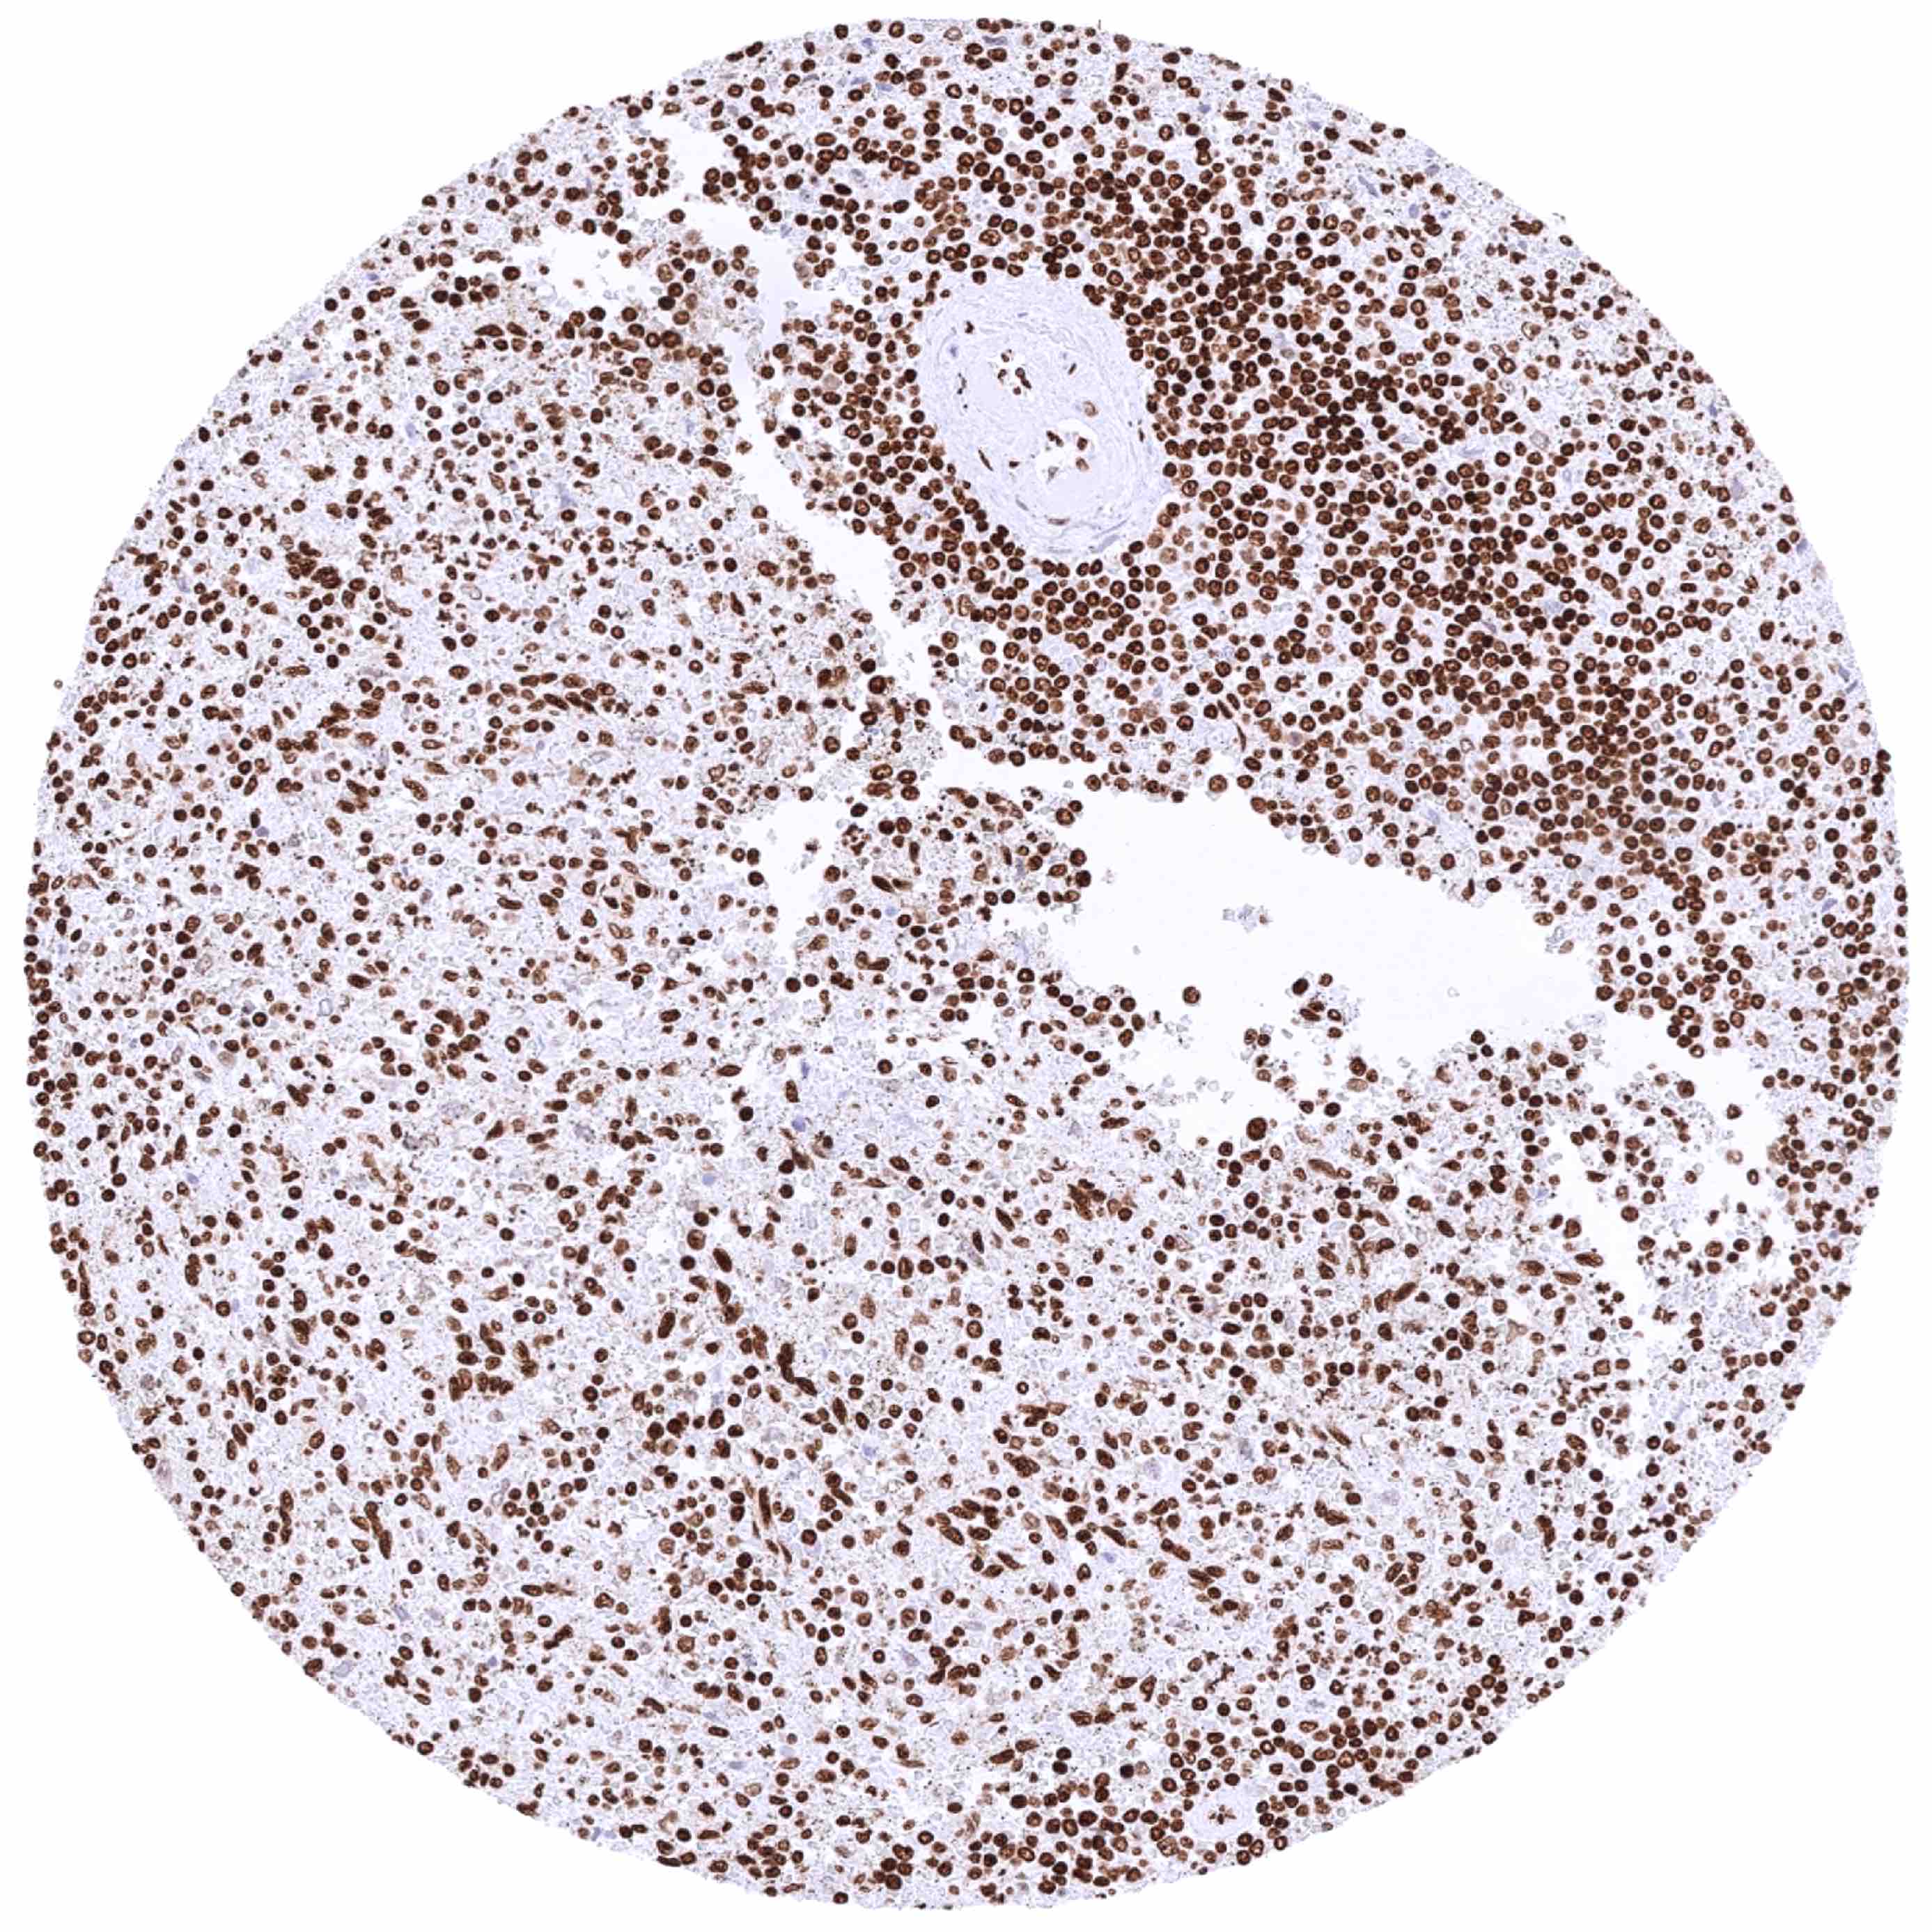

Bone marrow – Intense nuclear HMGB1 staining of virtually all cells of the hematopesis